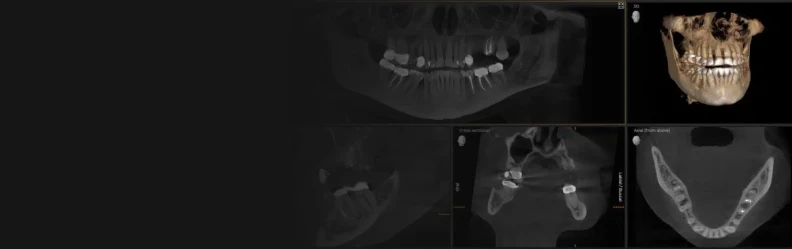

Advanced Dental Implant Technology in Tijuana

Precision, Comfort & Lasting Quality

From 3D imaging and guided surgery to premium implant systems, we invest in the latest technology to provide predictable, comfortable treatments. Every tool we use is chosen to enhance your safety and long-term success.

Technologies

Discover how our advanced technology ensures precision, safety, and lasting results. From 3D imaging to guided surgery, every tool enhances comfort and creates beautiful, predictable smiles you’ll love.